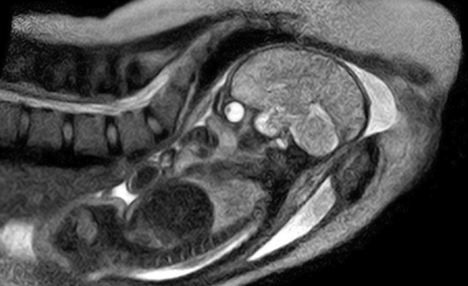

德國利用核磁共振成像拍出全球首套嬰兒降生圖片

核心提示:德國柏林沙里特醫院近日實現了一項醫學突破,他們首次成功利用核磁共振掃描,獲得了嬰兒降生過程的圖像。這些圖像是經一名德國孕婦同意后在核磁共振儀中分娩時被記錄下來的,使用的是一種特別的"開放式"掃描儀。醫院認為該圖像可為分娩過程提供有價值的認識。

中國日報網12月9日報道 據英國《每日郵報》12月7日報道,德國柏林沙里特醫院近日實現了一項醫學突破,他們首次成功利用核磁共振掃描,獲得了嬰兒降生過程的圖像。

這些圖像是在一個德國孕婦同意在核磁共振掃描儀里分娩后拍攝到的,它能夠為分娩過程提供一些有價值的新的認識,也可用于在將來拯救生命。

沙特林醫院的婦產科醫生恩斯特·拜茵德(音譯:Ernst Beinder)表示,該孕婦的整個分娩過程都很正常,機器拍下了孕婦子宮內的所有運動和整個分娩過程。“我們現在可以看到以前只能通過探針觀察到的全部細節,這些迷人的圖片再次證明了每個分娩都是一個小奇跡,”他說。

沙特林醫院研究團隊兩年前開始這項研究,本周終于取得成功。他們稱多名孕婦曾自愿參加這項實驗,另外還有5個孕婦的分娩過程將會被核磁共振掃描儀拍攝下來。醫院研究團隊為此還改進了通用的管狀核磁共振成像掃描儀,專門研制了一種特別的“開放式”掃描儀,以便為助產士和孕婦提供足夠的空間。

嬰兒出生過程的核磁共振成像圖片對于了解分娩并發癥至關重要,并能對大約15%需要接受剖腹產手術的孕婦的治療方案提供重要幫助。利用強大的磁體,核磁共振掃描儀能夠產生一個強大磁場,使無線電波探測到人體內的某些原子。研究人員則可用這些數據制作出患者身體的橫截面圖,提供軟組織和骨結構的細節。